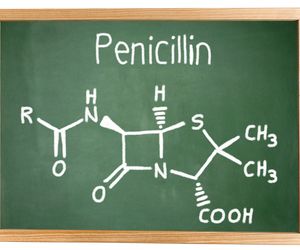

Alergia - inaczej uczulenie to nieprawidłowa reakcja organizmu na działanie substancji lub niektórych czynników. Choroby alergiczne są bardzo powszechne, a w krajach wysokorozwiniętych zmaga się z nimi około 30 proc. populacji. Uczulenie to nieprawidłowa, nadmierna reakcja układu immunologicznego na obce dla organizmu substancje. Objawy i stopień nasilenia alergii uzależnione są od rodzaju alergenu. Uczulenie najczęściej objawia się katarem, zatkanym nosem, kichaniem, dusznością i czerwonymi plamami na skórze.